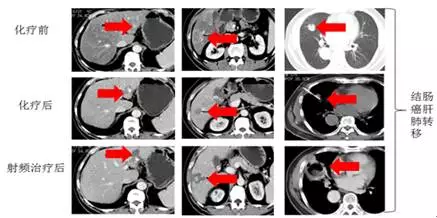

4.与化疗、放疗联合治疗。化疗、放疗联合射频消融治疗用于转移性肝、肺肿瘤,两者联合应用,可弥补各自的不足以增强疗效。对比任何一种单独治疗模式,延长了患者的生存时间,改善生活质量(见图5)。

图5:患者,男性,58岁,因结肠癌伴远处多发肝、肺多发转移,难以手术及治疗。结合化疗、靶向药物治疗,特别是结合微创射频消融技术成功无进展生存肝肺转移灶。